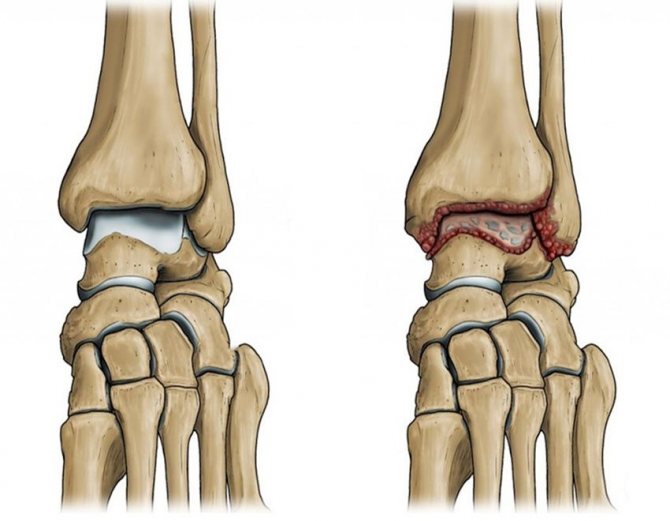

Голеностопный артрозо-артрит

Голеностопный сустав утрачивает прежнюю подвижность из-за повреждения хрящей, выстилающих поверхности большеберцовой, малоберцовой и таранной костей.

Вначале заболевание протекает бессимптомно, а последующие дискомфортные ощущения при ходьбе человек принимает за мышечную усталость. Поэтому пациенты обращаются к врачу уже при выраженных болях, свидетельствующих о костной деформации.

- Артрозо артрит голеностопа тоже встречается часто. При этом быстро теряется опорная функция ноги. Сустав деформируется, появляются сильные боли. Больной не может не только ходить, но даже немного двигать ступней.

Если артрозо-артритом поражен голеностоп, то пациенту показан артродез, заключающийся в полном обездвиживании сочленения. В последнее время в терапии используются стволовые клетки. Они замещают собой разрушенные участки хрящей, активизируют их регенерацию.